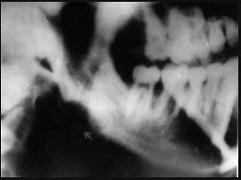

问题 常引起边缘性骨髓炎的间隙感染是()

选项 A.咬肌间隙 B.眶下颊间隙 C.颌下间隙 D.颏下间隙 E.颊间隙

答案 A